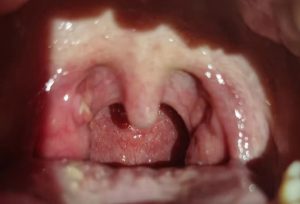

大女儿14号请假回家,惊人的是喉咙发炎已经是两边扁桃体红肿并且两边都有白色脓包堵住了喉咙,喝水也难,晚上发烧,喉咙很痛……期间去公益点三次,邹师姐帮忙按推,叮嘱在家温敷,含姜粉,100克姜片+一把参须煮水喝。24小时温敷脖子整整一圈。经历两个晚上痛到睡不着,含姜粉很痛,只能喷姜粉多次,16号早上女儿哭着说受不了了,想去打针。我也是心疼,女儿很能忍痛,也经过两个晚上痛到睡不到所以受不了了。只能安慰可以去的,只怕打针也不一定马上不痛呢。也许黎明的下一秒就是天亮了……接着16号晚上能睡了……期间也非常谨慎,温敷,姜汤一点都不敢马虎,加上自己的运动平甩功等。20号女儿完全可以吃饭中午去学校在学校继续保持暖贴在围脖温敷脖子,定时含姜粉,茶树精油刷牙,保持口腔清新健康。(茶树精油是植物中的消炎药,姜粉做温敷患处也有消炎作用)。

2021.10.14晚刚来公益中心时

2021.10.19

2021.10.20

前后对比